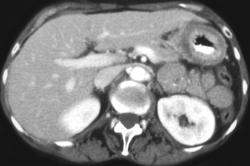

Linitis Plastica Stomach